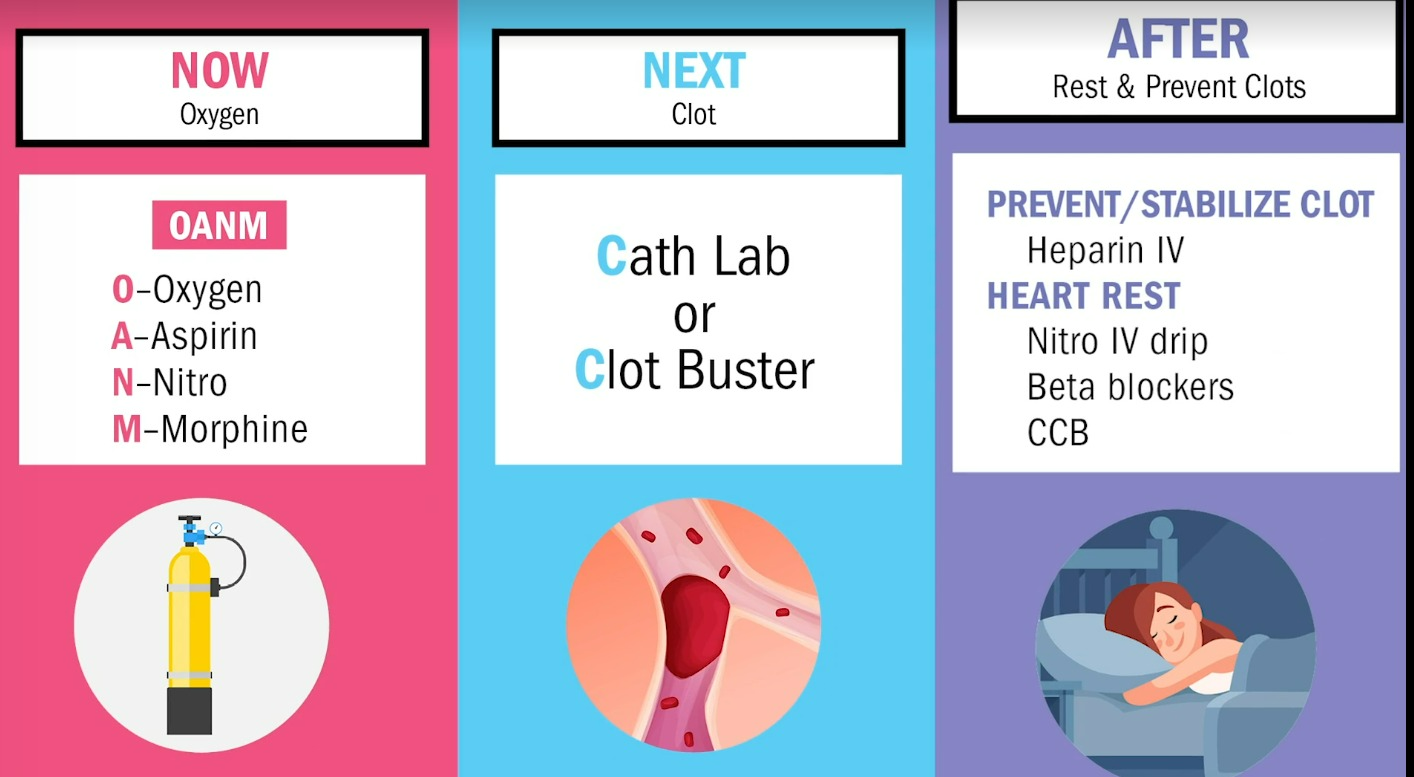

MI 중재(환자가 chest pain호소시 당장해줄수 있는것)

✔️O2

✔️Aspirin

✔️Nitro - ★주의사항 : 비아그라(-afil,Sildenafil절대금지 / 삼키지않고 혀밑에 녹이기 / 두통,혈압떨어지는건 예상된 반응 / 5분간격으로 3분까지만 복용하기 / 1번째 먹고 효과없으면 일단 구급차 부르고 2번째 약 먹기)

✔️Morphine : Morphine 투약 후 any chest pain = BAD! tissue death를 의미

===> 빠르게 Cath lab,

Clot buster 투약단계로 가야함

✔️Cath Lab 시술

여기까지 해서 살려놨으면 Rest, prevent clots 하는 after care 단계로 가야함

After Care

✔️Heparin IV : 혈전예방

✔️Nitro IV drip, Beta Blockers, CCB : heart 를 쉬게 해줌